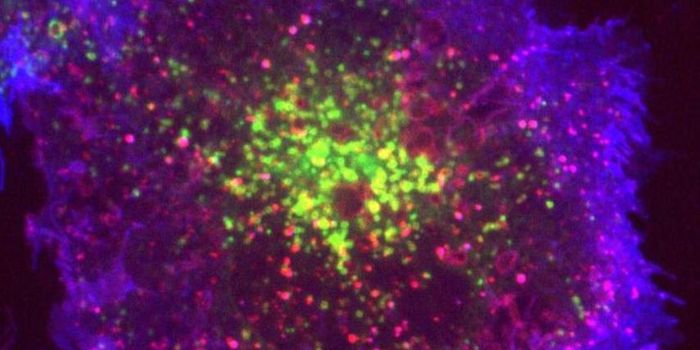

MAY 14, 2018ImmunologyFor the first time, scientists found that antibodies produced by the immune system can target multiple microbes, as oppo ...

FEB 09, 2018ImmunologyIt is the immune system’s duty to distinguish helpful bacteria from harmful bacteria. Thanks to millions of years ...